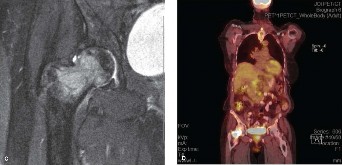

- Magnetic Resonance Imaging (MRI): Crucial for evaluating soft tissue extension, spinal cord compression, nerve root involvement, and intraosseous tumor extent. Helps delineate tumor margins, particularly for planning wide resections where appropriate.

- Positron Emission Tomography-CT (PET-CT): Useful for staging systemic disease, identifying additional lesions, and evaluating metabolic activity of the primary and metastatic sites.

Clinical and Radiographic Imaging